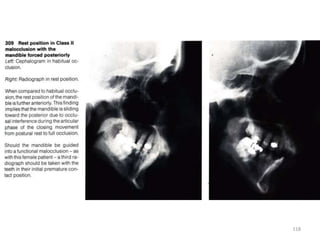

116

117

118

119